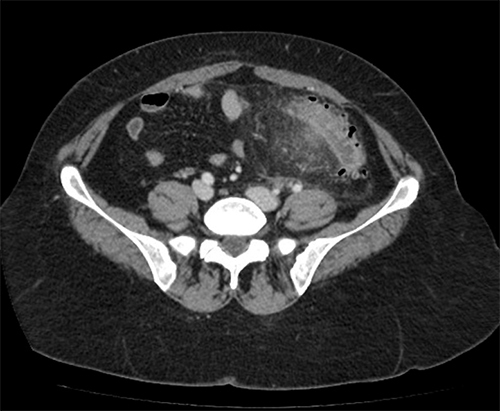

Monsieur A., 53 ans, est adressé aux urgences par son médecin traitant pour des douleurs abdominales fébriles. Celles-ci sont localisées en fosse iliaque gauche et hypogastre. Elles évoluent depuis quelques jours mais sont devenues plus intenses depuis vingt-quatre heures.

Cliniquement, il a une température à 38,2 °C, l’abdomen n’est pas distendu mais la palpation retrouve une franche douleur en fosse iliaque gauche et en hypogastre sans défense. Il n’y a pas de signe fonctionnel urinaire.

Le diagnostic est tout à fait possible, à évoquer ici en première intention devant l’âge (> 40 ans) et la symptomatologie (douleurs fébriles en fosse iliaque gauche et hypogastre).

– de la localisation de la douleur en fosse iliaque gauche ;

– du syndrome inflammatoire : fièvre à 38,5 °C avec hyperleucocytose à la biologie ;

– de l’argument de fréquence de cette pathologie à cet âge (la prévalence des diverticules sigmoïdiens est de plus en plus importante avec l’âge, après 40 ans).